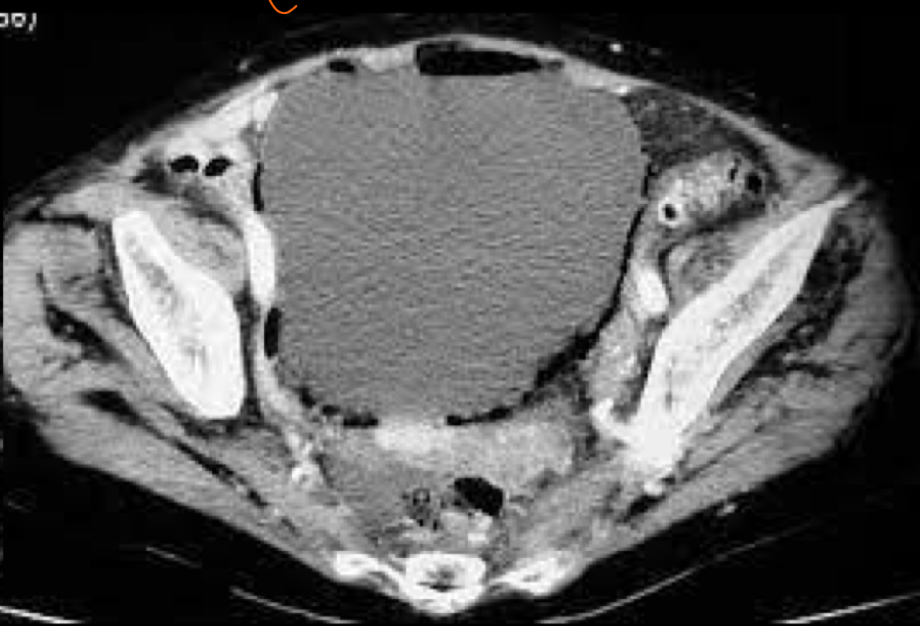

q se ve en US de la cistitis

A

• siempre con vejiga llena

• Paredes engrosadas

• Orina turbia

• Se ve ecos puntiformes: sedimiento urinario

Que se ve en tc de la cistitis

• Burbujas en pared: cistitis enfisematosa: DM2. Xq bacterias anaerobias llenas de gas

• Capta contraste